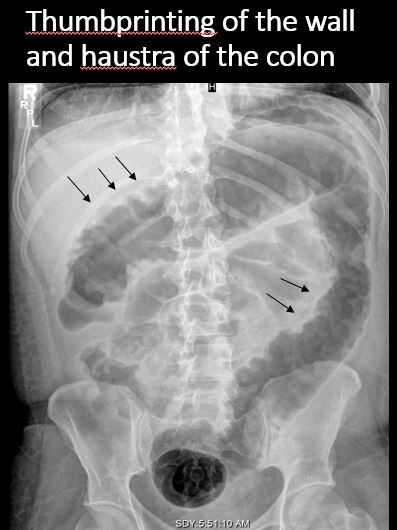

There is thickening or thumbprinting of the wall of the colon. [Yes/No]